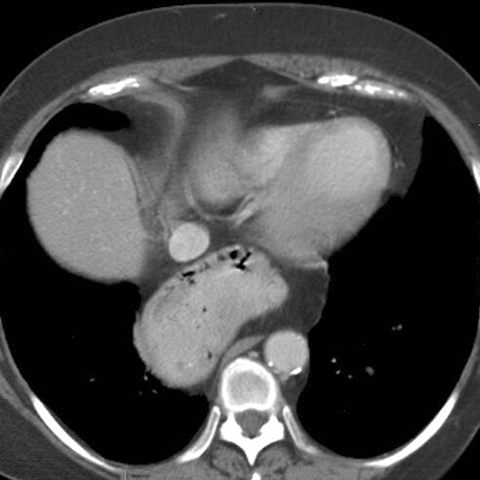

Paraesophagial Hernia, axial CT [2 of 2]